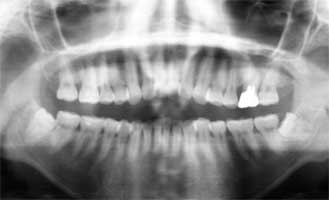

Fig. 19 Mr K 44 years old at the time of the first medical examination. Male

He had already lost three teeth of the upper jaw and the left second molar also need to be removed

Mr. K 44 years old at the time of the first medical examination. Male (Fig. 19-20)

He had already lost three teeth at the time of first medical examination. All remaining teeth had alveolar high bone destruction and if left they would all be lost by about 10 years later. Except for one intermediate year, he did not miss monthly scaling for 21 years after the first medical treatment. Consequently, the upper teeth functioned for 15 years and the lower teeth were maintained without any loss.